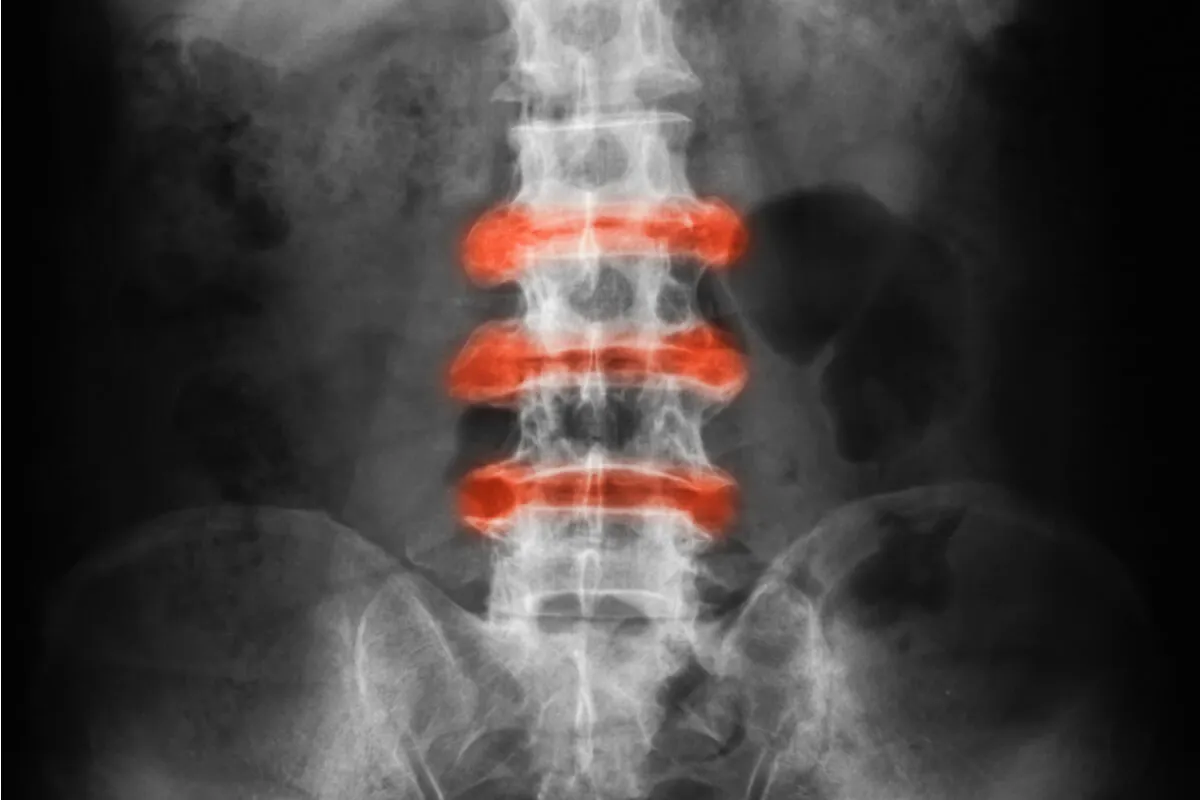

La espondiloartritis anquilosante es una enfermedad inflamatoria crónica que afecta fundamentalmente a las articulaciones de la columna vertebral.

Estas articulaciones tienden a soldarse entre sí, provocando una limitación de la movilidad. De esta forma hacen que la columna se vuelva menos flexible. Por esta razón, es muy común adoptar una postura encorvada hacia adelante.

Algunas de las áreas afectadas con mayor frecuencia son la articulación entre la base de la columna vertebral y la pelvis y las de las caderas. Sin embargo, también puede afectar a los puntos en los que los tendones y ligamentos se unen a los huesos, en especial en la columna vertebral.

Cuando hay espondiloartritis anquilosante, se forma hueso nuevo como parte del intento del organismo por curarse. Este nuevo hueso va cerrando el espacio entre las vértebras. De esta forma, se pueden fusionar secciones de una y otra vértebra.

Esas partes de la columna vertebral se vuelven rígidas e inflexibles. La fusión también puede agarrotar la caja torácica y disminuir la capacidad y función de los pulmones.

- Criterios radiológicos: como es la evidencia radiológica de inflamación de las articulaciones sacroilíacas.